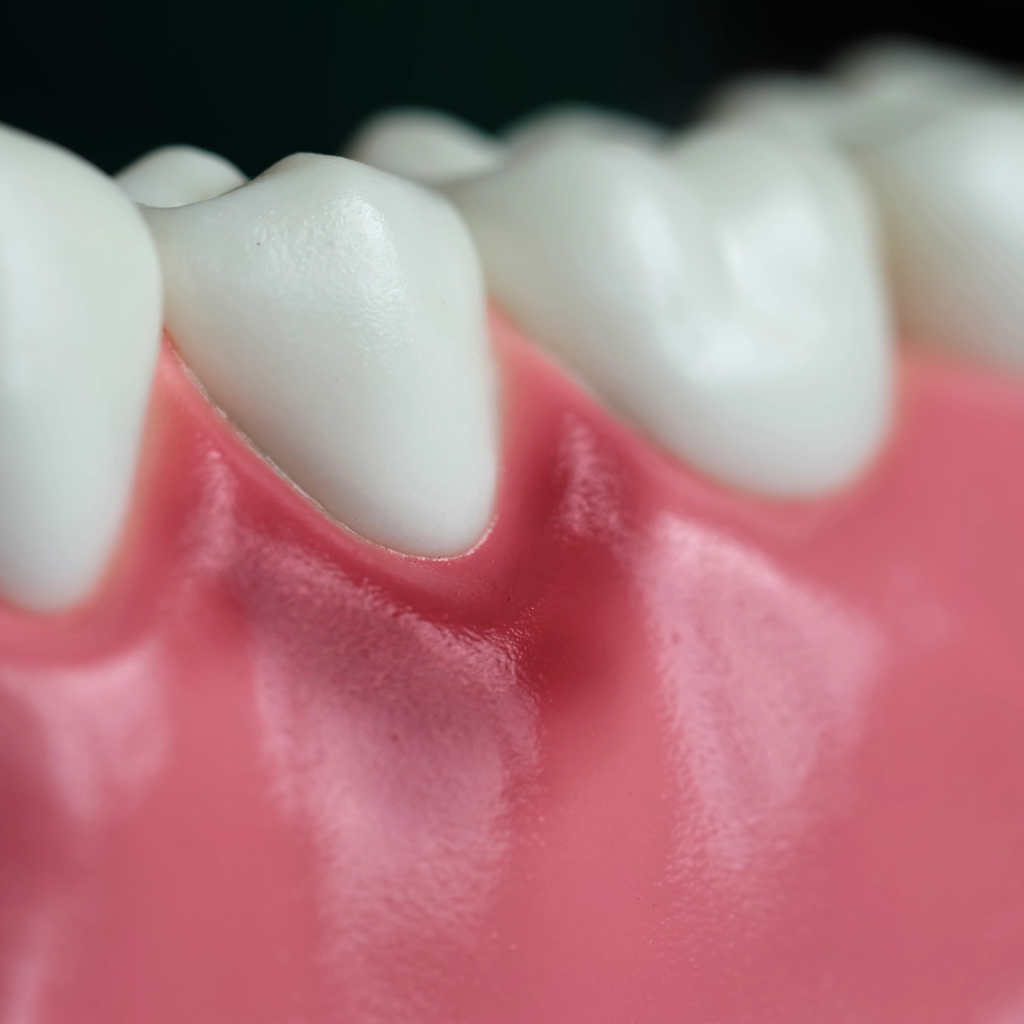

O que é o sangramento gengival?

O sangramento gengival ocorre quando as gengivas estão frequentemente inflamadas e sensíveis ao escovar os dentes ou ao usar fio dental e pode indicar problemas bucais subjacentes como gengivite ou periodontite.